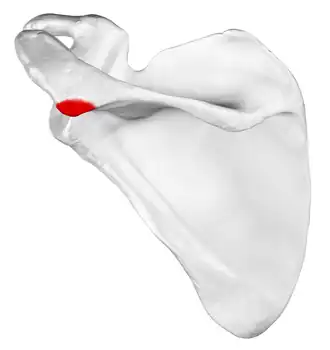

![]() Left scapula, posterior view. Acromion shown in red. | |

In human anatomy, the acromion (from Greek: akros, "highest", ōmos, "shoulder", pl.: acromia) or summit of the shoulder is a bony process on the scapula (shoulder blade). Together with the coracoid process, it extends laterally over the shoulder joint. The acromion is a continuation of the scapular spine, and hooks over anteriorly. It articulates with the clavicle (collar bone) to form the acromioclavicular joint.[1]

Structure

The acromion forms the summit of the shoulder and is a large, somewhat triangular or oblong process, flattened from behind forward. It projects laterally at first, then curves forward and upward to overhang the glenoid fossa.[2] It starts from the base of acromion which marks its projecting point emerging from the spine of scapula.[3]